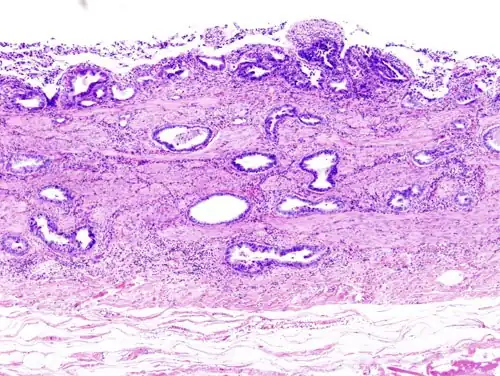

-

Gallbladder adenocarcinoma lymphatic invasion histopathology -

Incidentally discovered gallbladder cancer (adenocarcinoma) following a cholecystectomy. -

Gallbladder adenocarcinoma histopathology